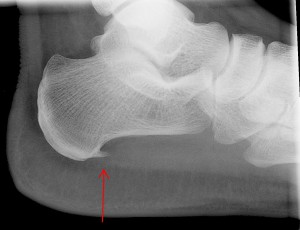

Plantar Fasciitis causes pain under your heel. It can be unpredictable and strike indiscriminately — it seems mine was triggered by wearing sneakers for a couple of days in a row.  I had just bought TWO pairs of these cute converse style lace ups from Kurt Geiger thinking how stylish and sensible (good for my bad back and achy knees …that’s a whole other story).

FasciitisIt is easy to diagnose and GPs are familiar with the classic symptoms.  Mainly a hot flash of pain as you take your first steps of the day across the bedroom. The pain re occurs during the day particularly if you sit for a while and then start walking again.

Currently every morning when I get-out of bed my right foot has a really sharp unpleasant pain underneath by the heel as I put my weight on it.  Now I have to wear orthotics inside my shoes, visit a physiotherapist and do exercises.  If I’m diligent it should improve. Although I gather that there isn’t a cure for this condition.  I’m fortunate that I have medical insurance with Bupa and so I managed to get to see a top foot and ankle doctor Mr Martin Klinke from The London Foot & Ankle Centre.  Mr Klinke was kind and thorough. As part of his care I also visited Rina Bimbashi a top Podiatrist also part of The London Foot & Ankle Centre.

Apparently this is a very common complaint and guess what, if you are overweight you will be more susceptible to getting it.